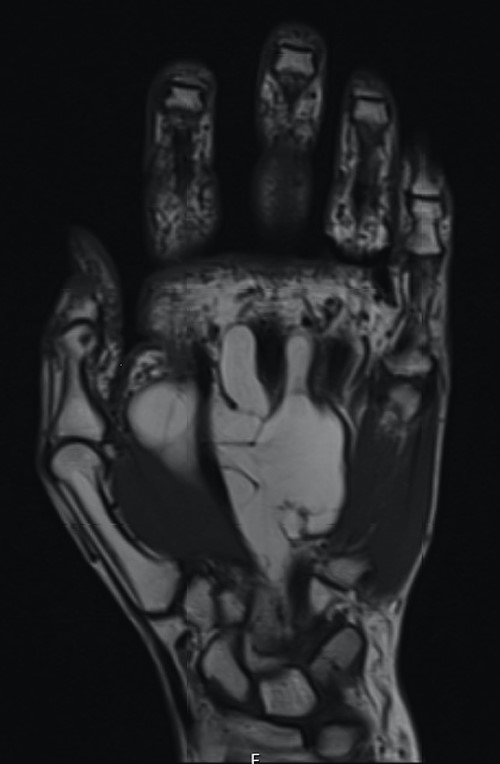

The patient underwent an elective marginal excision under brachial plexus block and tourniquet haemostasis. A volar approach with an extended carpal tunnel release was utilized to access the lesion (Fig. 3). Given the MRI findings of the dorsal extent of the tumour, a dorsal incision was considered and marked pre-operatively. However, this was ultimately not required, as adequate access was achieved using the volar approach to excise the entirety of the lipoma. A multi-lobulated, encapsulated fatty lesion was found in the central palm extending to the carpal tunnel and the dorsal sub-aponeurotic space, involving the third inter-metacarpal space and flexor tendons. The tumour was successfully resected en bloc whilst protecting all tendons and neurovascular structures. The excised lesion measured 12 × 7 × 2.4 cm (Fig. 4). After excision, satisfactory haemostasis was achieved; drain inserted and skin closed using absorbable sutures. No immediate postoperative complications were noted.

Intraoperative images demonstrating the relationship of the lesion with the surrounding neurovascular structures.